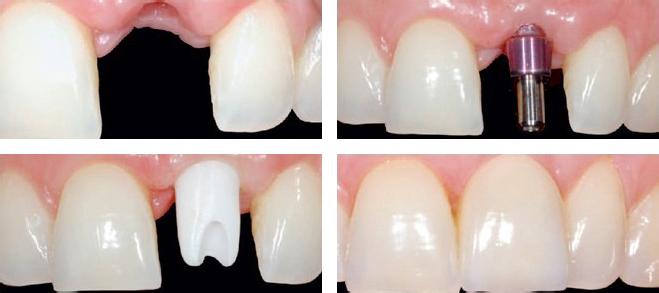

一、先进的种牙

广州越秀圣贝口腔门诊部口腔采用的是自引进的种植牙,是对口腔牙列缺损、牙列缺失修复的先进,种牙快速、,修复的牙齿宛如真牙,成功治疗案例超过50万。

三、个性化的种植方案

广州越秀圣贝口腔门诊部口腔聘请的医生都是拥有二十年以上种植经验的著名专家,可以根据每位患者的具体情况,量身制定的种植牙方案,让种植牙手术更加精准。>>>详情点击咨询牙管家

四、的种植牙品质

圣贝牙科的每一颗种植体均系原装进口,全部严格通过ohsas18000连锁健康认证以及ISO9000连锁质量认证,种植体享受5年全国质保,并终身提供维护服务。【阅读:种植牙会不会很疼】